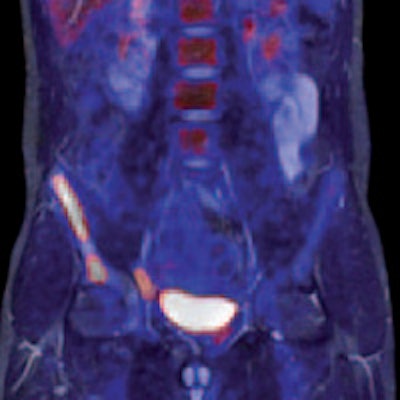

Philips has been working on its latest MR technology for almost as long as the search for a practical PET/MR hybrid. After an eight-year development project, the company is promoting its Ingenia 1.5- and 3-tesla systems, which it describes as the world's first digital broadband MR unit. This incorporates dStream architecture, which digitizes the signal directly in the coil. Vendors have been looking for ways to shorten the analogue part of the signal processing pathway because this offers the potential for reducing signal loss and noise. The Philips approach goes further by digitizing the signal within the coil itself and transporting it via a fiber-optic cable to the acquisition electronics contained in the scanner cabinet, explained Maurits Wolleswinkel, global lead for MR marketing.

The company had to overcome huge challenges in miniaturizing the components to fit inside the coils and making them tough enough to cope with the hostile physical environment inside the machine, with its strong magnetic fields, eddy currents, and temperature changes. "The result offers a gain of up to 40% in the signal to noise ratio and a 30% improvement in throughput, and eliminates the need for coil/channel upgrades as the system is totally channel-independent," he stated. "So it is a significant step forward, especially in oncology-related applications. They become better, faster, and more robust. We can do a total liver examination, including contrast, in less than eight minutes, or a whole-body diffusion scan in 15 minutes."

Two-station torso imaging with multitransmit. Image courtesy of Philips.